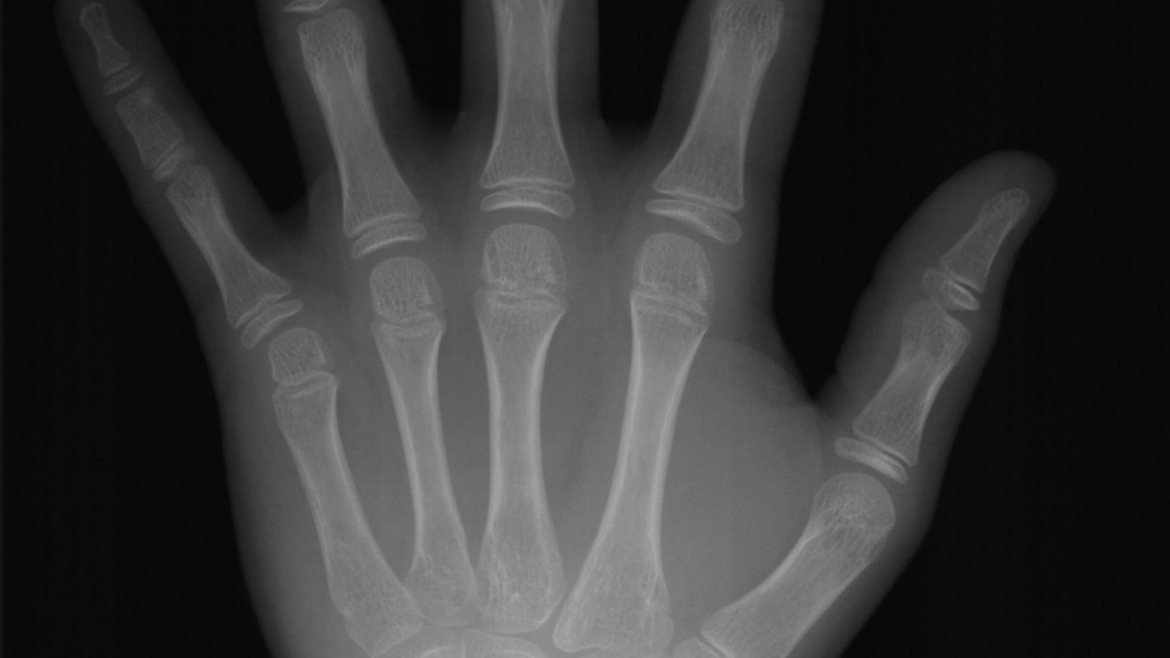

A radiografia de mão e punho é utilizada para determinar a idade óssea através a possibilidade de avaliação da maturação dos ossos. Esse exame auxilia na determinação da curva de crescimento do paciente, estimando seu estágio de desenvolvimento. É um importante aliado no planejamento de tratamentos ortodônticos/ortopédicos de crianças e adolescentes.